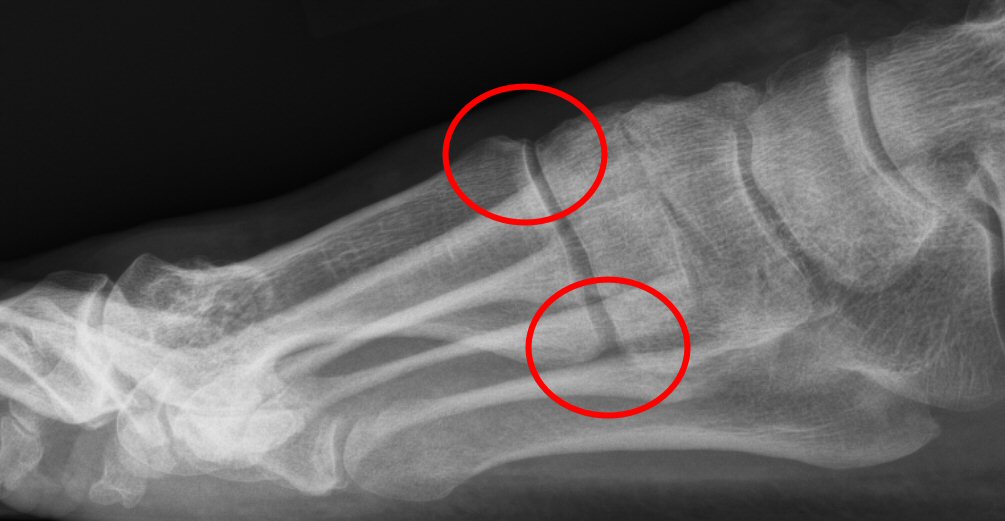

Fot med hallux valgus, markerad hallux-valgusvinkel

Intermetatarsalvinkel (IM-vinkel): vinkel mellan metatarsale 1 och 2, normalt 10-12°.

Fot med hallux valgus, markerad intermetatarsalvinkel

Tecken till instabilitet i TMT1: minskad ledspringa dorsalt